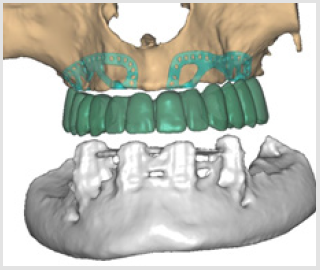

Subperiosteal implant design started with the processing of CBCT images. Figure 1 shows STL files of the patient’s mandibula, which is the lower jawbone. Figure 2 shows STL file of the patient’s maxilla, which is the upper jawbone. Figure 3 shows the result of virtual planning with the maxilla, mandibula, the designed implant, and denture. The final subperiosteal implant was designed based on CBCT images. Mechanical aspects were also considered in the design process of the titanium framework. Figure 4 shows the STL file of our titanium implant design with its three-dimensional geometry that had been analysed with finite element method.